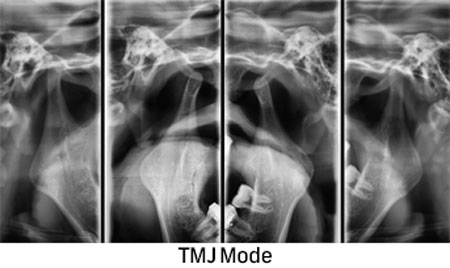

2D и 3D CBCT РТГ ДИГИТАЛНА ДИЈАГНОСТИКА

Преку нашите истражувачки активности, нашиот тим е запознаен со најновите научни наоди и може да ги исполни највисоките технолошки и професионални очекувања. За прегледи и проценки, имаме широк спектар на опции. Користиме различни методи за сликање, како што се проекциона радиографија, томографија и компјутерска томографија.

Kористиме најнова технологија за да овозможиме прецизен третман за нашите пациенти преку методи на снимање.